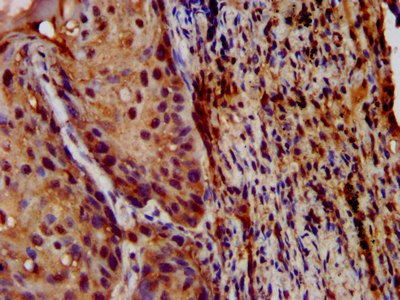

IHC image of CSB-PA848833LA01HU diluted at 1:200 and staining in paraffin-embedded human prostate cancer performed on a Leica BondTM system. After dewaxing and hydration, antigen retrieval was mediated by high pressure in a citrate buffer (pH 6.0). Section was blocked with 10% normal goat serum 30min at RT. Then primary antibody (1% BSA) was incubated at 4°C overnight. The primary is detected by a biotinylated secondary antibody and visualized using an HRP conjugated SP system.